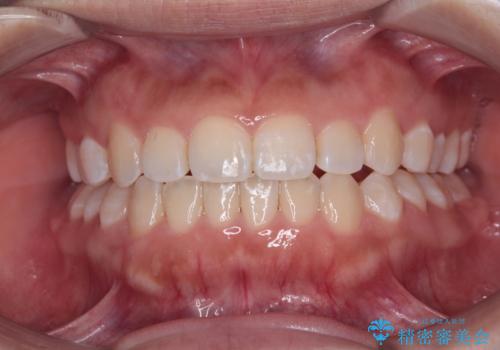

前歯のデコボコを抜歯矯正で改善 メタル装置で費用を抑える

非抜歯矯正ではデコボコを解消することでより口元が突出してしまうため、上下左右の小臼歯4本の抜歯を行い、ワイヤー装置による矯正治療を行うこととしました。

もう少し口元の突出感を改善したかったのですが、舌の突出癖が影響し下顎前歯が唇側に押させる仕上がりとなりました。